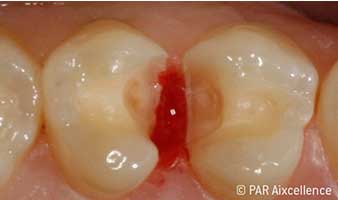

Рис. 5. На этапе экскавации четко виден кариозный процесс; апроксимальные фиссуры, как кажется, не содержат измененных тканей

Рис. 6. Изображение, как на рис 5, на этот раз с использованием Facelight. Теперь кариес четко распознается и в фиссурах